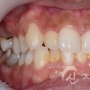

치아교정 치료사례